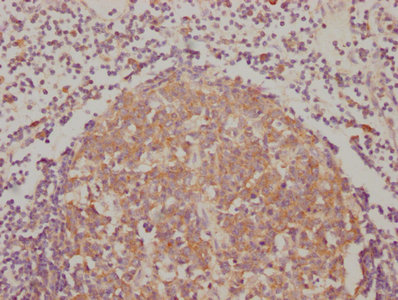

IHC image of CSB-RA624111A0HU diluted at 1:90 and staining in paraffin-embedded human lymph node tissue performed on a Leica BondTM system. After dewaxing and hydration, antigen retrieval was mediated by high pressure in a citrate buffer (pH 6.0). Section was blocked with 10% normal goat serum 30min at RT. Then primary antibody (1% BSA) was incubated at 4℃ overnight. The primary is detected by a biotinylated secondary antibody and visualized using an HRP conjugated SP system.